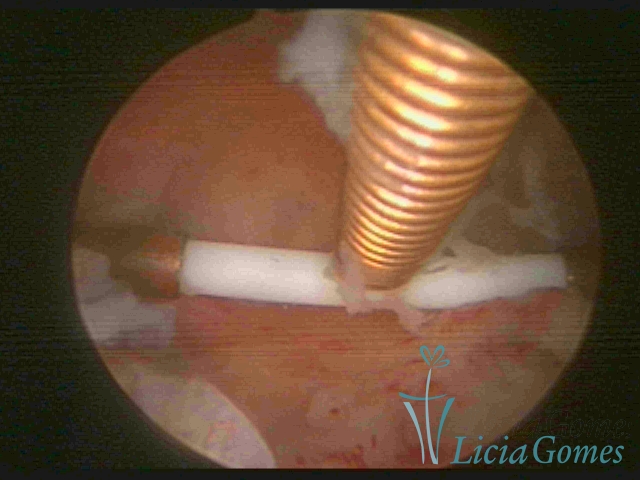

Cavidade com o Mirena®, sendo retirado sob visão direta